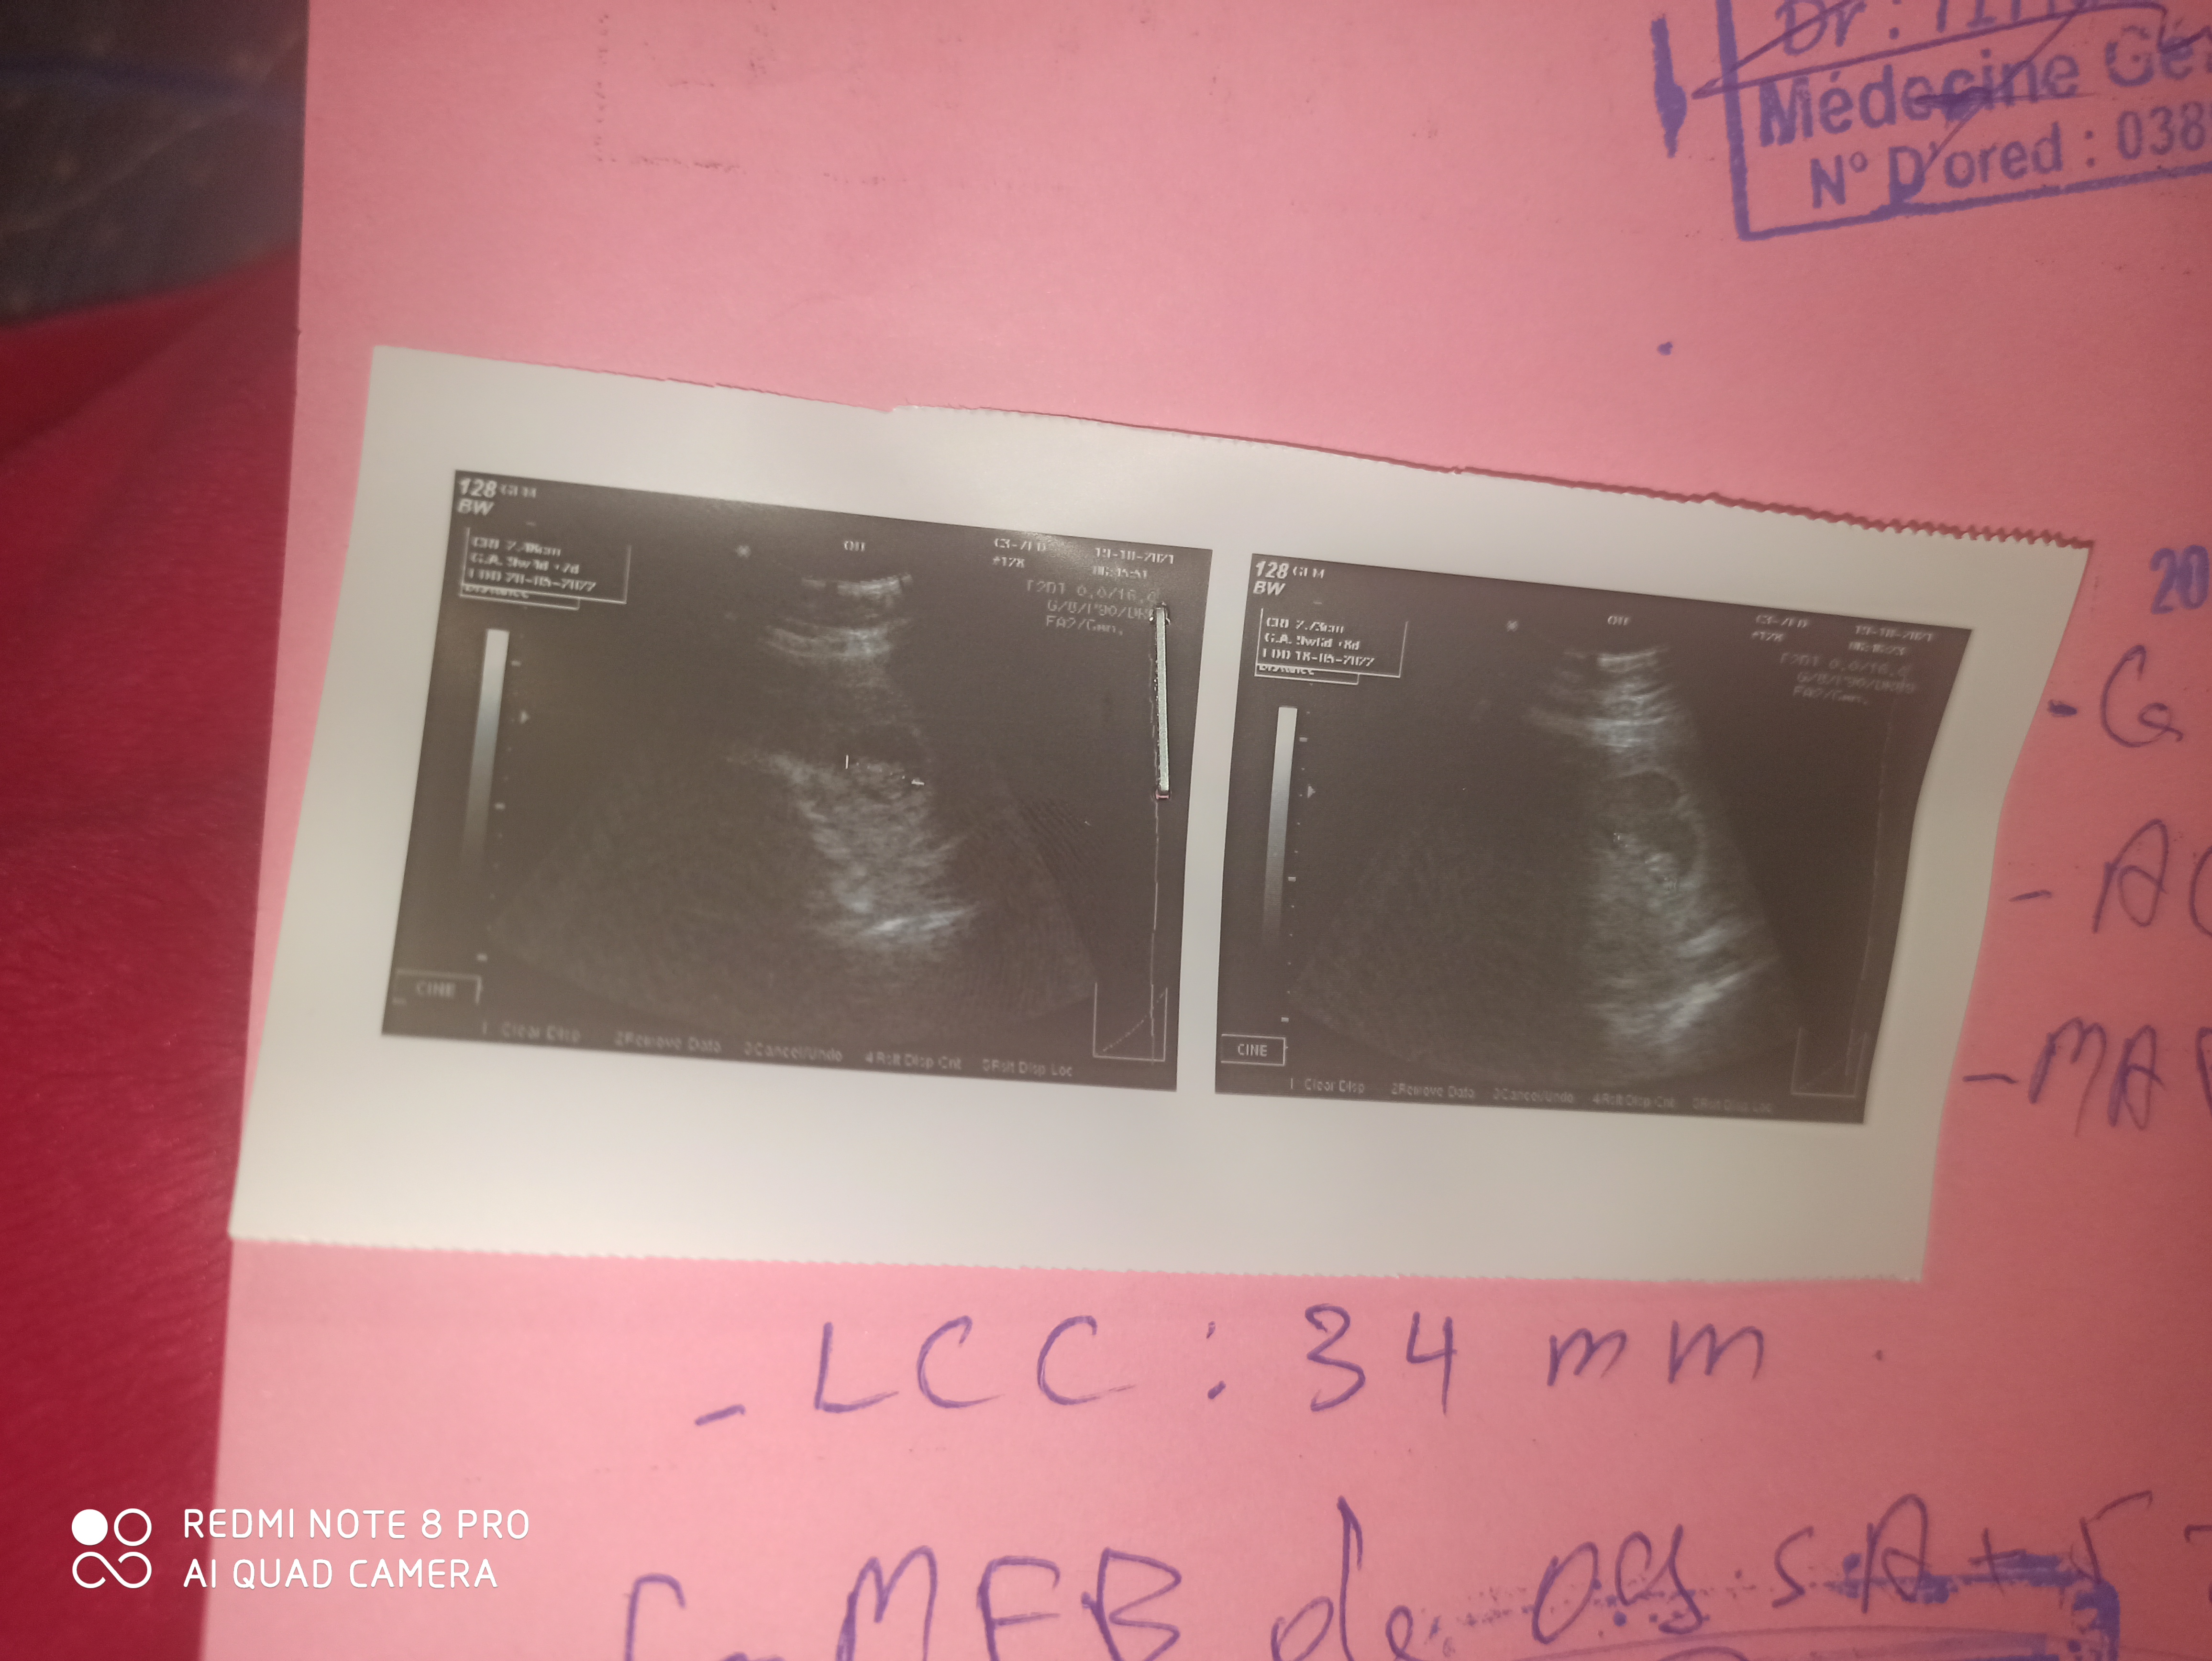

هل توام او جنين ارجوك اكدلي